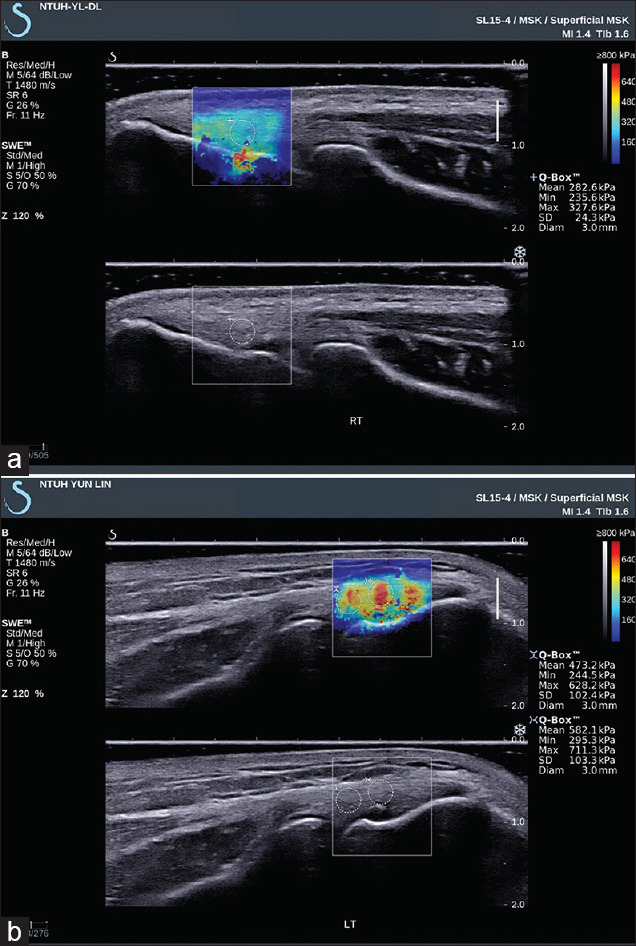

Methods: This cross-sectional case-control study included 30 manual workers with unilateral LET (LET group) and 30 age- and sex-matched healthy volunteers (control group). Demographic data collection and functional evaluation were performed using the Disabilities of the Arm, Shoulder, and Hand; Patient-Rated Tennis Elbow Evaluation; and European Quality of Life Five-Dimensions questionnaires. Physical examination of the elbows and evaluation of the common extensor tendon (CET) with B-mode morphology ultrasonography and Young's modulus elastography were performed. The LET-unaffected and LET-affected elbows in the LET group were compared with the elbows in the control group.

Results: The LET-unaffected elbows in the LET group had a higher prevalence of positive chair test results and focal hypoechoic change and microcalcification on ultrasonography than those in the control group (P < 0.05, 0.005, and 0.05, respectively). In addition, LET-affected elbows showed higher focal hypoechoic change, microcalcification, erosive cortex, and neovascularity than elbows in the control group (P < 0.001, 0.001, 0.005, and 0.001, respectively). The unaffected and affected elbows showed greater CET thickness than those in the control group (P < 0.05 and 0.005).